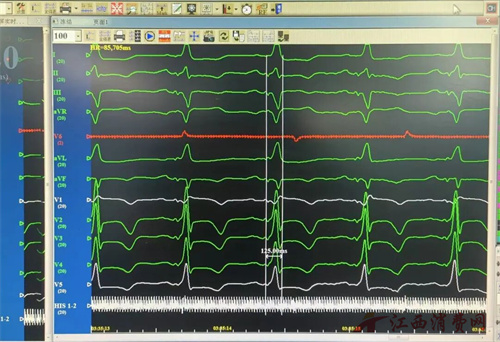

55岁的朱先生罹患扩张型心肌病五年,长期受心力衰竭折磨。尽管历经规范的优化药物治疗,其病情仍持续进展:心脏显著扩大、收缩无力,心脏射血分数(LVEF)降至仅37%(正常人通常在50%-70% 之间),更关键的是其心电图呈现严重的左束支传导阻滞(QRS波宽度>187毫秒),导致左右心室收缩严重不同步。

一个月后复查的结果令人欣喜,心脏超声:射血分数从37%提升至46%,左心室大小从51毫米回缩至48毫米。这意味着心脏泵血力量显著增强,扩大的心脏开始“缩小”。心电图:原有的左束支传导阻滞图形明显改善,QRS波宽度从大于187毫秒显著缩短至120毫秒,阻滞的左室开始同步收缩,心室的收缩活动基本恢复了协调同步。

这些客观数据清晰地证实了Lot-CRTD治疗的有效性,同时朱先生自觉胸闷、气短水肿的症状得到了完全缓解,已经开始进行运动康复了。